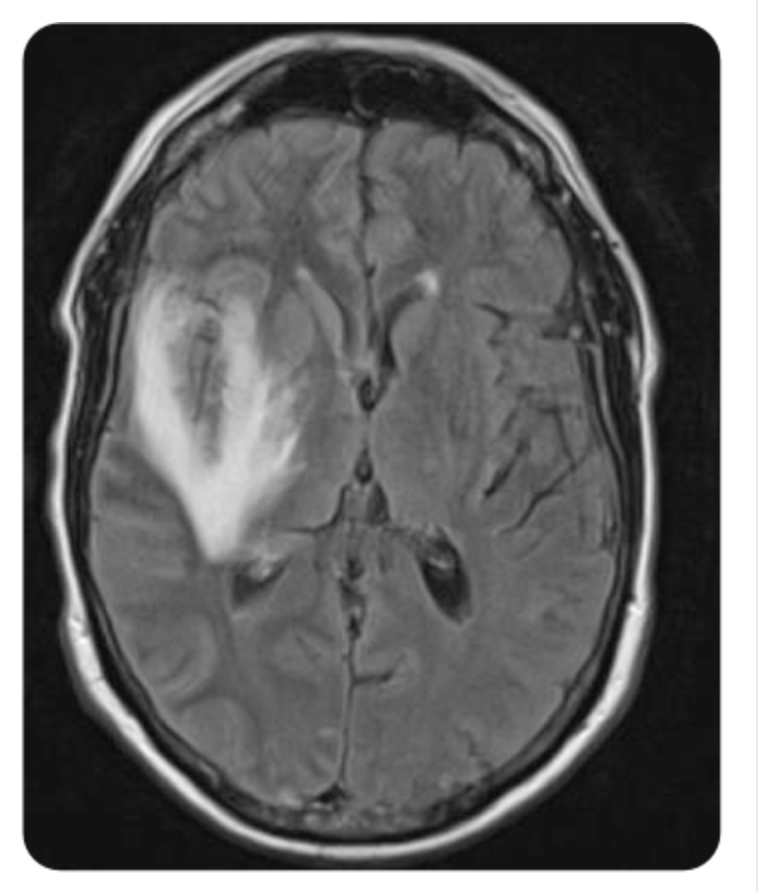

Q

What dx?

Pt has abnormal brain function. may have a prodrome of flu-like illness. Symptoms often include headache, fever, change in behavior, and speech abnormalities. Seizures can also develop.

A

Encephalitis (swelling most likely in the temporal lobe as shown by brain MRI)